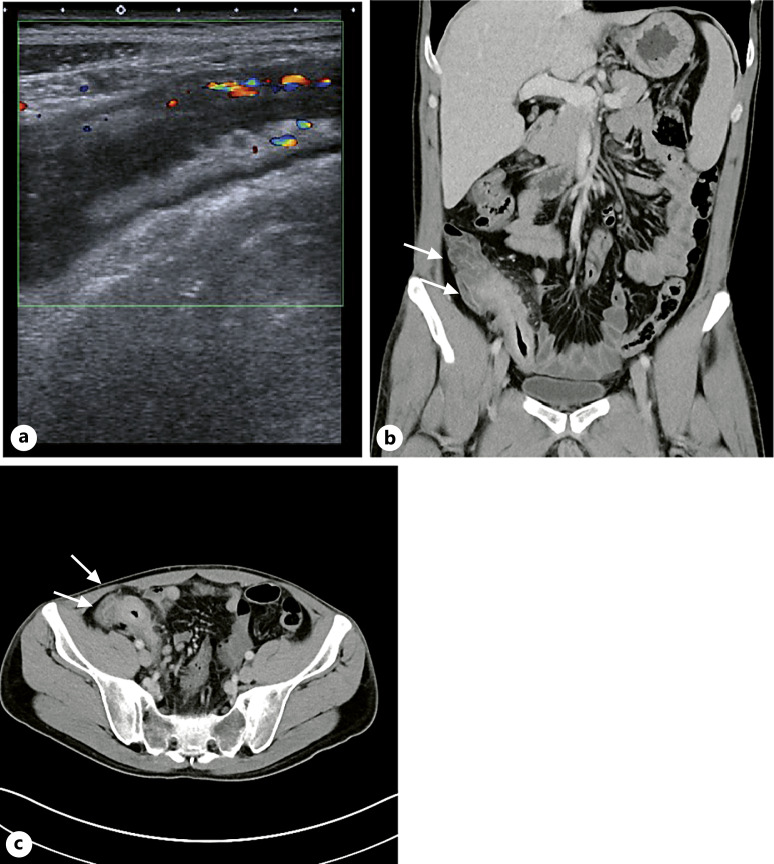

Case presentation: Our patient initially presented with axSpA at the age of 27. Nine years later, CD was diagnosed by the age of 36. One year after the diagnosis of CD, a spontaneous ileal perforation occurred as part of a disease course refractory to multiple anti-TNF antibodies and intolerance to immunomodulators. However, the axSpA showed a response to the anti-TNF certolizumab pegol. After stopping certolizumab pegol, we enrolled the patient into the M15-991 induction trial (MOTIVATE) and the maintenance trial (FORTIFY) testing the anti-IL-23 antibody risankizumab versus placebo in CD with failure to prior biological therapy. As a result, risankizumab induced a CD response but failed to control the axSpA. Considering the CD refractory and the axSpA responding to anti-TNFs, we initiated a DTT with risankizumab and certolizumab pegol. Risankizumab and certolizumab pegol together improved both CD and axSpA. As adverse events, there were only two episodes of spontaneously resolving common colds during the 19-month reviewed period.